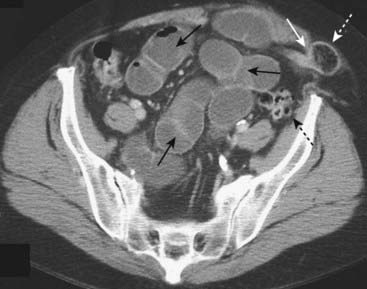

But if the intracolonic pressure rises high enough and the ileocecal valve opens (such a valve is called incompetent), then gas from the dilated large bowel decompresses backward into the small bowel, much like the air escaping from a balloon.

This can produce a picture in which there is disproportionate dilatation of the small bowel compared to the decompressed large bowel. This picture mimics that of a mechanical small bowel obstruction (Fig. 14-14).

Figure 14-14 Large bowel obstruction masquerading as a small bowel obstruction.

There are air-filled and dilated loops of small bowel (solid white arrows) seen in this patient who had a mechanical large bowel obstruction from a carcinoma of the middescending colon. The pressure in the colon was sufficient to open the ileocecal valve, which then allowed much of the gas in the colon to decompress backward into the small bowel. The cecum still contains air (dotted white arrow) and is dilated, a clue that this is really a large bowel obstruction. Abdominal CT can resolve the question of whether the large or small bowel is obstructed.